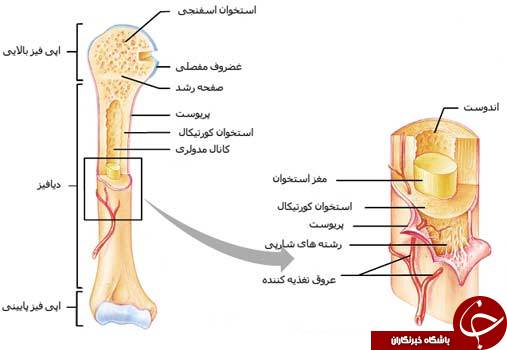

اسکلت داربست بدن است تمام قسمت های بدن روی اسکلت قرارگرفته اند بدن انسان از ۲۰۶ قطعه استخوان تشکیل شده است این استخوان ها طوری با نظم کنار هم قرار گرفته اند که انسان را قادر می سازد حرکات دقیقی داشته باشد. استخوان یک نسج بسیار محکم است زیرا در ترکیب آن منرالها مانند کلسیم و دیگر وجود. اسکلت داربست بدن است تمام قسمت های بدن روی اسکلت قرارگرفته اند بدن انسان از ۲۰۶ قطعه استخوان تشکیل شده است این استخوان ها طوری با نظم کنار هم قرار گرفته اند که انسان را قادر می سازد حرکات دقیقی داشته باشد. آناتومی سه بعدی بدن انسان عکس گرافی بدن امعاء و احشاء بدن آناتومی سه بعدی بدن انسان عکس گرافی بدن امعاء و احشاء بدن قلب کبد روده.